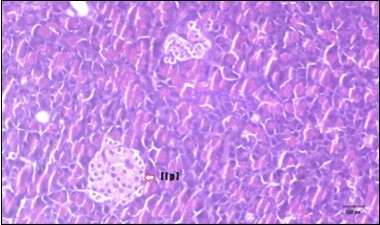

Pancreas Histopathological Observations

Histological examination of pancreas of the control rats showed normal sized islets of pancreas (Ip) compared to the diabetic rats which showed markedly atrophic islets of pancreas (I.p.) (Figure 8 and Figure 9). Pancreas of in groups (3) and (4) rats showed mild atrophic islets of pancreas (I.p.) with inflammatory cellular infiltrate (Figure 10 and Figure 11). The pancreas of rats in group (5) showed nearly normal islets of pancreas (I.p.) with few inflammatory cellular infiltrate (I.c.) (Figure 12).

Figure 9.Photomicrogragh of pancreas section of diabetic rat showing the markedly atrophic islets of Langerhans. (arrow) (H&E) (40X).

Figure 10.Photomicrogragh of pancreas section of treated rat with Fenugreek showing less improved islets of Langerhans with more cells (star). (H&E) (40X).

Figure 11.Photomicrogragh of pancreas section of treated rat with Glimepiride showing mildly improved of isled of Langerhans with large number of cells (dashed-arrow). (H&E) (40X).

Figure 12.Photomicrogragh of pancreas section of treated rat with both Fenugreek and Glimepiride showing nearly normal islets of Langerhans with spindle (arrow) & polygonal cells (dashed- arrow). (H&E) (40x).

Histopathological observation in diabetic control showed degenerative changes in both endocrine and exocrine pancreases. A probable explanation may be related to oxidative stress resulting from hyperglycemia which decreases the antioxidants levels and increases ROS 33 and the activities of antioxidant enzyme were altered in diabetic rats. These effects further exacerbate the development and progression of diabetes complications and these may represent the causes of degeneration revealed in histological sections. Fenugreek improved blood glucose levels and insulin, lowered pancreatic islet and β-cells damage which may be attributed to its immune modulatory activity and insulin stimulation action along with its antioxidant potential 32. Glimepiride caused restoration of morphology of beta cell of diabetic and it increased percentage of beta cells 34. This protective effect could be attributed to the antioxidant properties of Glimepiride. Combination therapy improves the protective effect of both therapies alone.